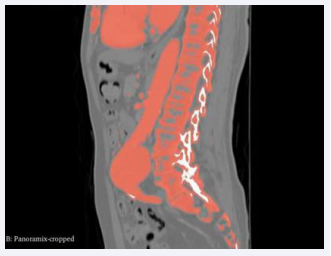

Utilizing Computed Tomography (CT) abdomen scans procured from online repositories such as 3D Embody and the NHIA database in NRRD file format with sagittal, axial and coronal view of abdomen CT. A meticulous 1-1 reconstruction of the abdominal cavity of patients was meticulously orchestrated employing the open-source software known as 3D Slice ran advanced tool designed for scientific data visualization (Figure 1).

Source volume panoramic cropped.

Figure 5: Source volume panoramic cropped.